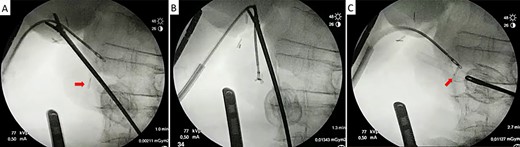

With the patient in supine position, the trocars were placed as per the American technique of LC. After releasing lax adhesions, the remaining cystic duct was recognized and individualized from the CBD with cold scissors. Once isolated, a lateral incision in the cystic stump was made for CBD exploration (Fig. 3). Under radiological guidance, the clip was successfully removed through the cystic duct with endoscopic hose-type biopsy forceps (Fig. 4). A control cholangiography confirmed CBD clearance (Fig. 5). At the end of the procedure, the metallic clip was removed from the abdominal cavity (Fig. 6), and the remnant cystic stump was secured with a PDS Endoloop Ligature in order to avoid any future migration (Video 1 shows our technique). The patient recovered uneventfully and was discharged 3 days after surgery.

Laparoscopic transcystic extraction under intraoperative radiological guidance. Without any contrast injection to facilitate titanium visualization, the metallic clip (red arrow) is recognized in the distal CBD (A), caught with the endoscopic forceps (B) and finally removed from the CBD through the cystic duct (C).